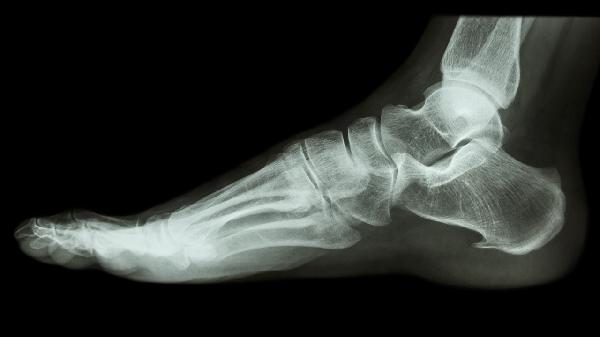

右脚第二个脚趾骨折怎么恢复

右脚第二脚趾骨折可通过制动固定、药物治疗、物理治疗、康复训练、手术治疗等方式恢复。第二脚趾骨折通常由外伤、骨质疏松、长期劳损等因素引起。